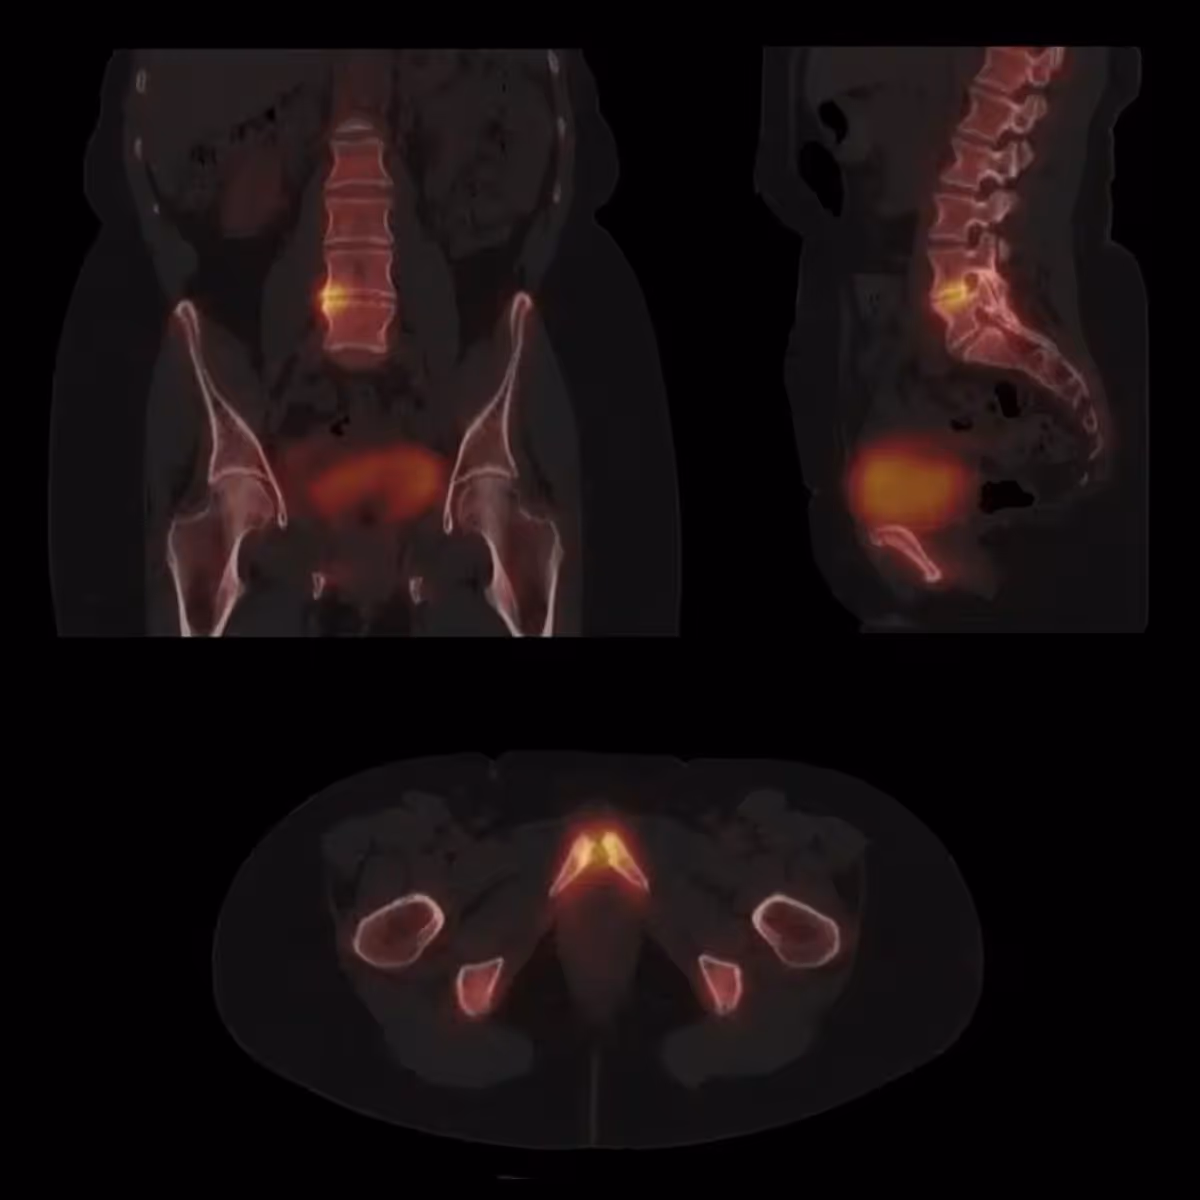

Symbia Intevo Skeletal Pathology

OSTEITIS PUBIS AND DEGENERATIVE LOWER LUMBAR SPINE

(Image credit: www.siemens-healthineers.com)